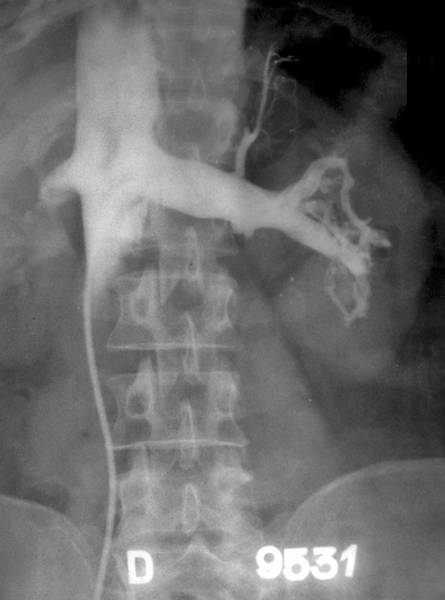

АНТЕГРАДНАЯ ПИЕЛОГРАФИЯ

Антеградная пиелография — рентгенологический метод исследования ВМП, основанный на непосредственном введении контрастного вещества в ЧЛС. Его осуществляют двумя путями: пункцией ЧЛС и введением в неё контрастного вещества или контрастированием по ранее установленной нефростоме (рис.). Пункцию ЧЛС и антеградную пиелографию выполняют в тех случаях, когда на экскреторных урограммах отсутствует выделение контрастного вещества, а проведение ретроградной уретеропиелографии невозможно (малая ёмкость мочевого пузыря, уретрит или простатит, непроходимость мочеточника, вызванная стриктурой, облитерацией, опухолью и др.). Внедрение КТ и МРТ позволило практически полностью отказаться от этих диагностических процедур. Антеградная пиелография после пункции ЧЛС — один из этапов малоинвазивных чрескожных оперативных вмешательств на почке и ВМП (пункционной нефростомии, нефролитолапаксии), выполняемых под рентгеновским контролем.

Антеградная пиелоуретерограмма справа: расширение чашечно-лоханочной системы; стеноз лоханочно-мочеточникового сегмента.

Антеградную пиелографию как самостоятельный диагностический метод обычно применяют при наличии нефростомы. Она позволяет судить о морфологическом и функциональном состоянии ВМП: размерах лоханки и чашечек, их тонусе, степени и причинах нарушения оттока мочи из лоханки в мочевой пузырь. Кроме того её применяют для обнаружения конкрементов, определения локализации и протяжённости стриктуры мочеточника и др. При хорошем тонусе ВМП обычно сразу отмечают продвижение контрастного вещества по мочеточнику. Возникновение у больного ощущения тяжести и боли в пояснице при введении контрастного вещества указывает на то, что давление в почечной лоханке выше допустимого. Антеградную пиелографию при соответствующих показаниях считают весьма ценным диагностическим методом, но он не заменяет, а дополняет основные методы рентгенодиагностики заболеваний почек и ВМП.